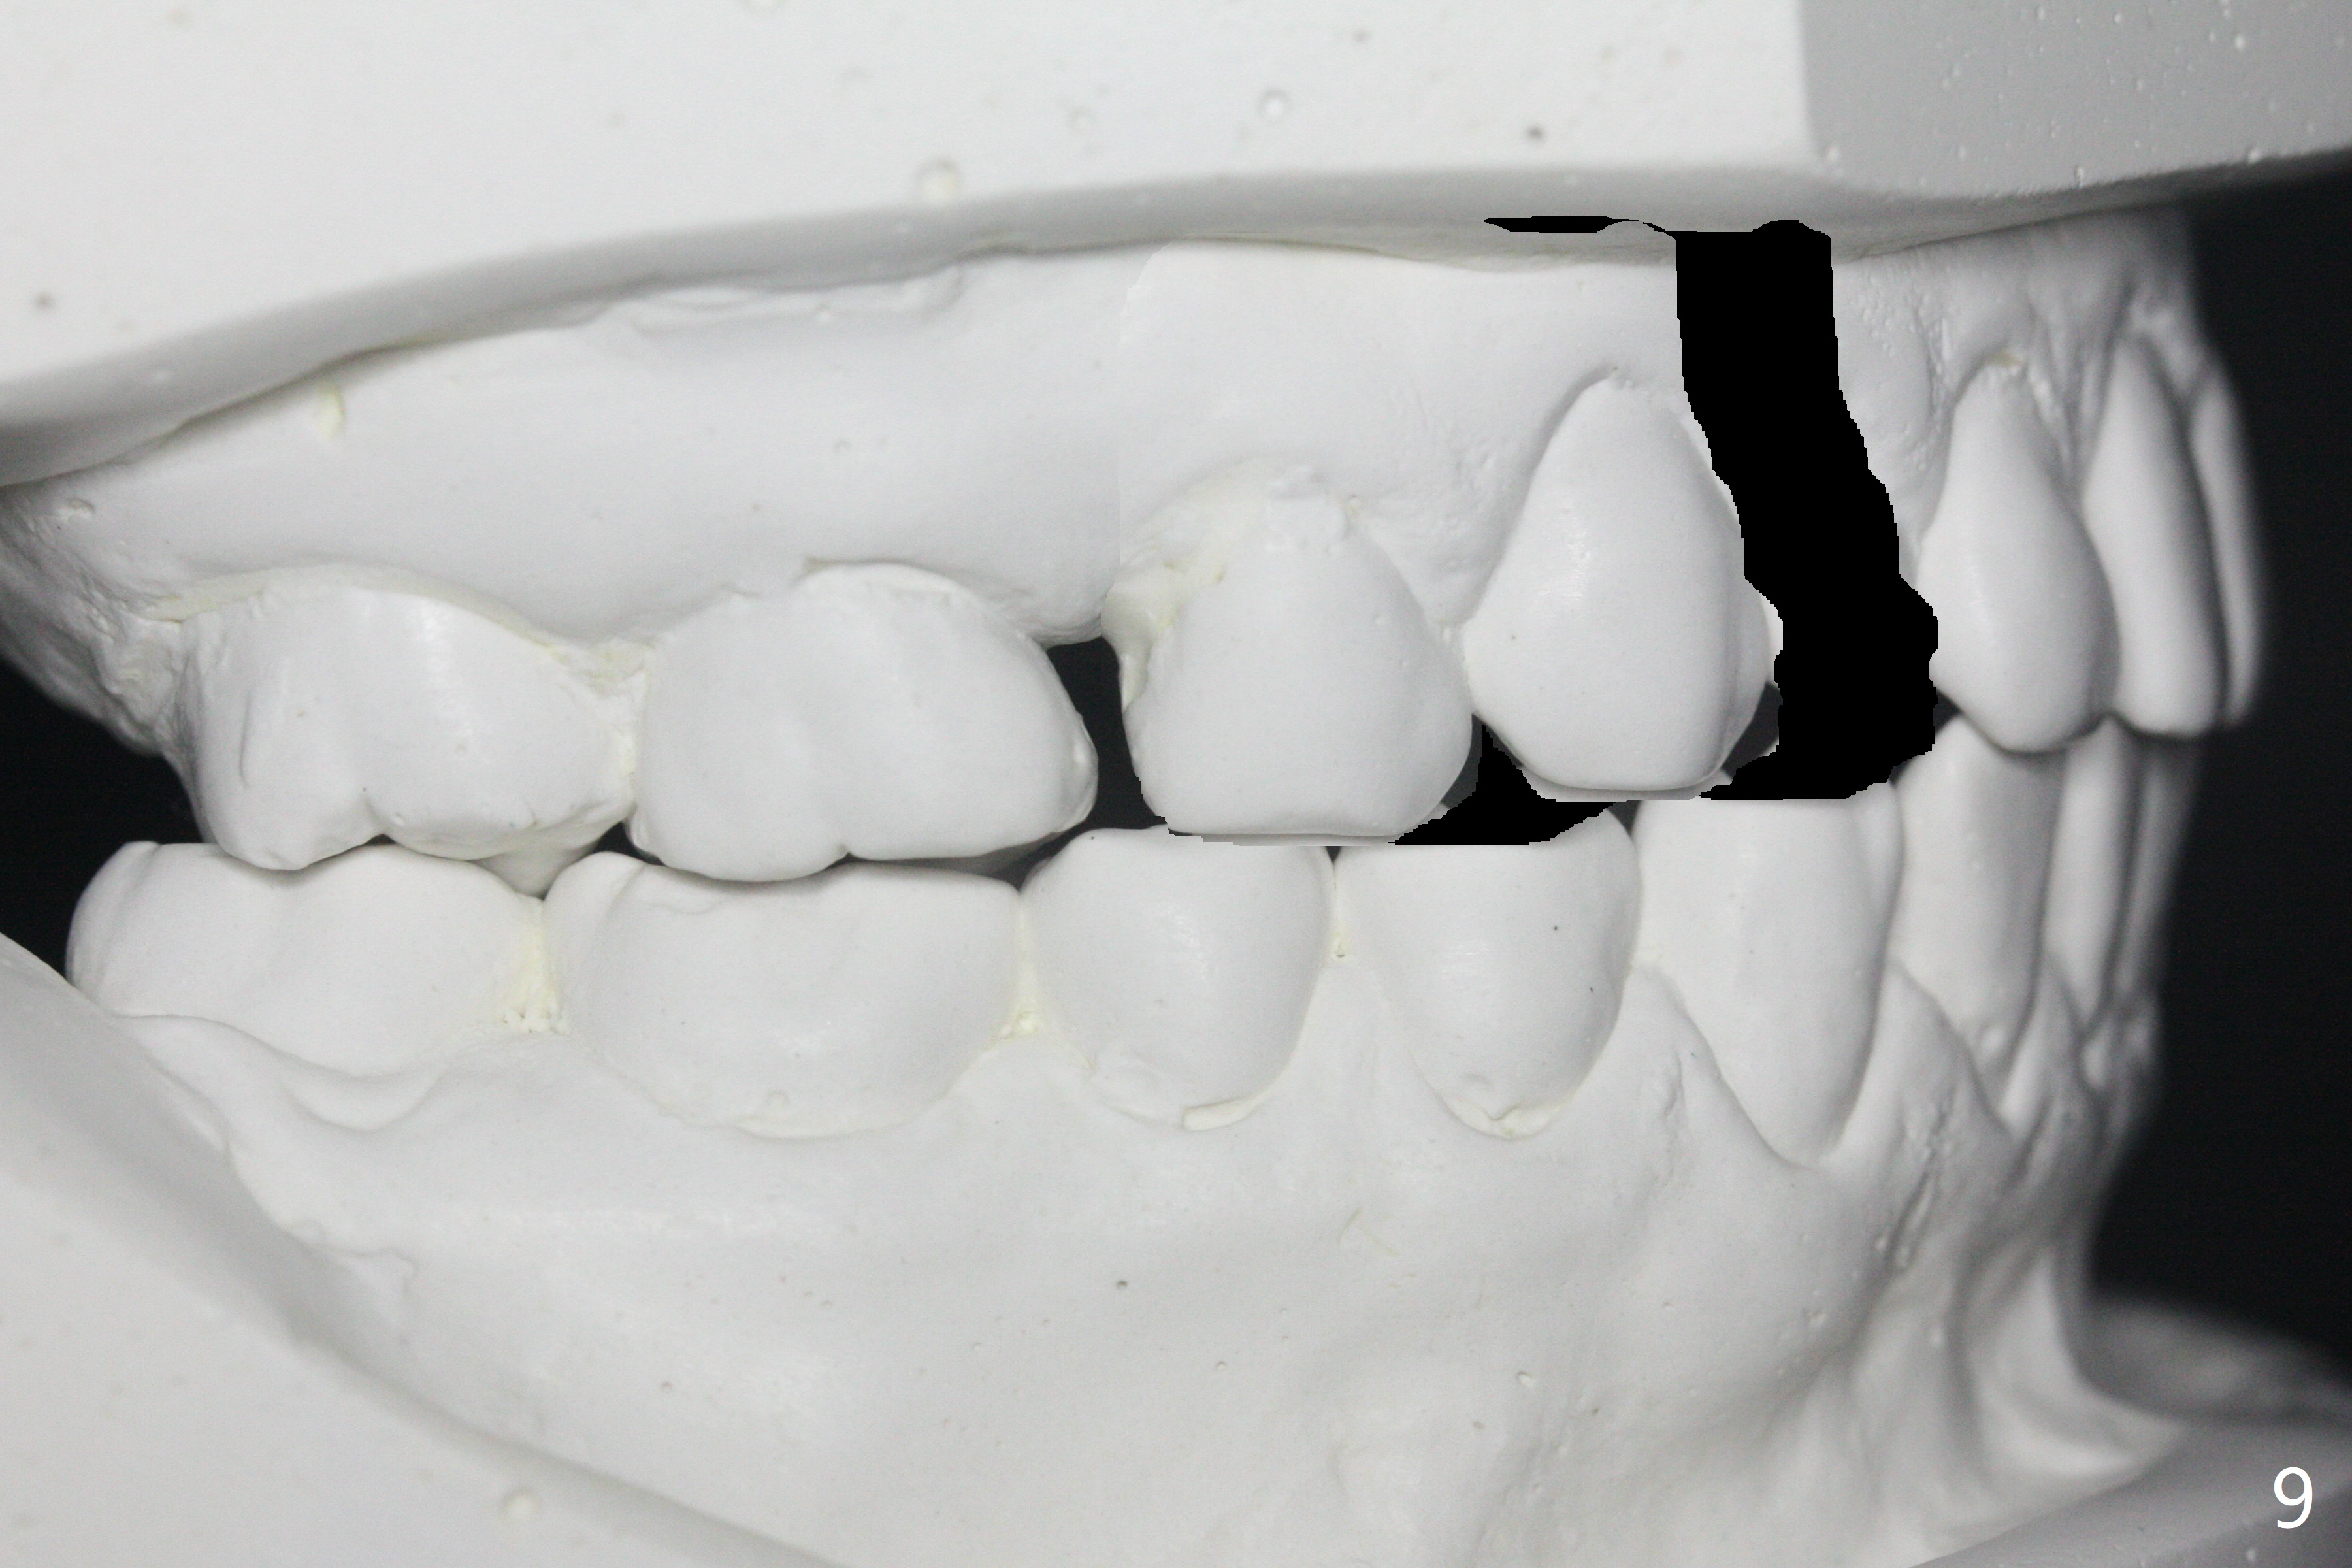

A 40-year-old man requests orthodontics after #17 and 32 extraction. UL5 is missing (Fig.1), while the upper midline deviates to the left (Fig.2 arrow) with crowding between UL2 and 3 (Fig.3). The main goal is to retract UL5 distal and move the upper midline to the right to alleviate UL anterior crowding. Implant will be not needed. To monitor potential root resorption associated with tooth movement, preop PAs are taken (Fig.4-7). The space for an implant at UR5 is narrow. UR4 needs to be distalized using UR7 or a miniimplant distal to UR7 as an anchor (Fig.8). UR4 and 3 will be repositioned to establish Class I occlusion (Fig.9). The space gained by UR4 distalization may be enough to correct the upper midline deviation and UL3 malposition (Fig.10). Brackets will be placed in the lower arch in spite of the normal alignment (Fig.11). UL2 and 3 brackets are unable to be engaged to 14 niti wire (Fig.12). Next visit try to engage UL2 bracket. If not, save the old wire for possible future reuse. Closed spring is placed with 18 ss wire <3 months post banding (coronavirus). Three weeks post closed spring between UR4-7, UR3,4 are being distalized (Fig.13). Distalization of UR4 is not much in 5.5 months (Fig.14,15). It seems necessary to use a miniimplant distal to UR7 as an anchor (Fig.16 white circle), place a long hook mesial to UL4 (more or less root movement instead of tilt) and place the same closed spring between the anchor and hook. In spite of the fact that UR4 seems to have been completely distalized and that UR2 is being distalized 8 months post banding (Fig.18), a 8 mm long mini-implant is placed in the maxillary tuberosity with minimal local anesthetic (Fig.17,19). A longer closed spring (18 mm) is placed between the implant and UR3 hook (Fig.20). Next appointment a lingual button will be placed at UR4 for rotation, while a post hook mesial to UR3 for torque. UR3 distalizes with the help of UR mini-implant, which is unfortunately loose. Next visit place lingual button at UR4 (Fig.21 arrow) to distalize the lingual cusp. Crimpable power hook is placed mesial to UR2 for distalization (for root torque, Fig.22). If it works, remove the wire and reposition the hook for UR1 next visit. UR2 is distalized in one appointment (~ 1 month, Fig.23, as compared to Fig.22). With lingual button at UR4, rotation seems to have been corrected shortly (Fig.24 arrow).